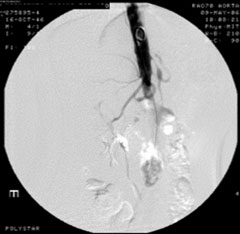

症例8

58歳 男性

左間歇性跛行(150m)

平成18年1月より間欠性跛行出現。

平成18年3月近医受診しASOと診断され、Cilostazolにて保存的に加療するも改善なし。

6月当院紹介受診。

【既往歴】

胃潰瘍

54歳 脳梗塞(内服)

高血圧(+) 糖尿病(−) 喫煙歴(10本×30年)

ABI:右1.0 左0.6

【治療計画】

Bilateral CIA Stenting (Kissing stent with Palmaz stent)

症例8 MRA